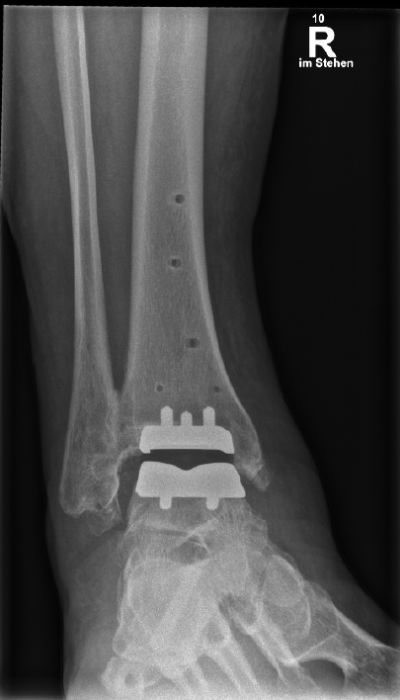

Seitliche Röntgenaufnahme des rechten Sprunggelenks mit eingesetzter Prothese und Fixierungsschraube im Fersenbein.

Abbildung a-d: 78-jähriger Patient mit viertgradiger OSG-Arthrose bei varischer Verkippung des Talus. Verlaufskontrolle 6 Wochen nach Implantation der OSG-TEP. Noch erkennbare Bohrlöcher in der Tibia von der Ausrichtungslehre der OSG-TEP.

Seitdem ist eine umfangreiche technische Entwicklung des Designs, der Implantatbeschichtung und der Implantationstechnik vollzogen worden (17-19). Lange hatte die Endoprothetik des OSG mit kurzen Standzeiten und Komplikationen zu kämpfen. Die heute zur Verfügung stehenden Konzepte kommen den Standzeiten der Hüft- und Knieendoprothesen immer näher (20). Während früher Fehlstellungen im OSG als Ausschlusskriterium betrachtet wurden, erfolgt heute die Achskorrektur durch Osteotomie ein- oder zweizeitig im Rahmen der Implantation der Endoprothese (Abbildung c,d). Wichtig ist die sorgfältige Behandlung von Inkongruenzen im Sprunggelenk mit Wiederherstellung des korrekten Alignments. Wird die Fehlstellung regelrecht behoben, sind die biomechanischen Resultate vergleichbar mit denen ohne vorbestehende Inkongruenz (21). Studien konnten zeigen, dass bei Varus-Fehlstellung bis zu 30° präoperativ nach Prothesen-Implantation mit erfolgtem Re-Alignment kein relevanter Unterschied im funktionellen Outcome zu betrachten ist (22).

Der Patient, 78 J., männlich, stellte sich mit seit Jahren bestehenden, progredienten Schmerzen im rechten OSG in der Sprechstunde vor. Klinisch zeigte sich eine plantigrade Fußstellung bei varischer Rückfußachse. Die Beweglichkeit war eingeschränkt, Dorsal-/Plantarflexion OSG rechts 0/0/35°. Motorik, Durchblutung und Sensibilität waren intakt. Im Röntgen wurde eine viertgradige OSG-Arthrose bei ausgeprägter varischer Verkippung des Talus und Synostose des distalen Tibiofibulargelenkes deutlich. Nach Ausschöpfung der konservativen Therapiemaßnahmen stellten wir die Indikation zur Implantation einer OSG-TEP mit ergänzender minimalinvasiver Umstellungs­osteotomie des Calcaneus. Postoperativ erfolgte die Mobilisation im langen Walker mit Bodenkontaktlauf. 6 Wochen postoperativ lagen reizlose Narbenverhältnisse vor. Das Bewegungsausmaß stellte sich mit Dorsal-/Plantarflexion 10°/0°/40° verbessert dar. Es bestand noch eine moderate Schwellneigung. Im Röntgen zeigte sich eine gut integrierte OSG-Endoprothese bei unveränderter Implantatlage und knöchern fusionierter Calcaneus-Osteotomie. Von Seiten des Patienten bestand eine deutliche Reduktion der Schmerzen und subjektive Zufriedenheit. Anschließend erfolgte eine rasche Steigerung der Belastung bis zur Vollbelastung ohne Walker und Gehstützen.